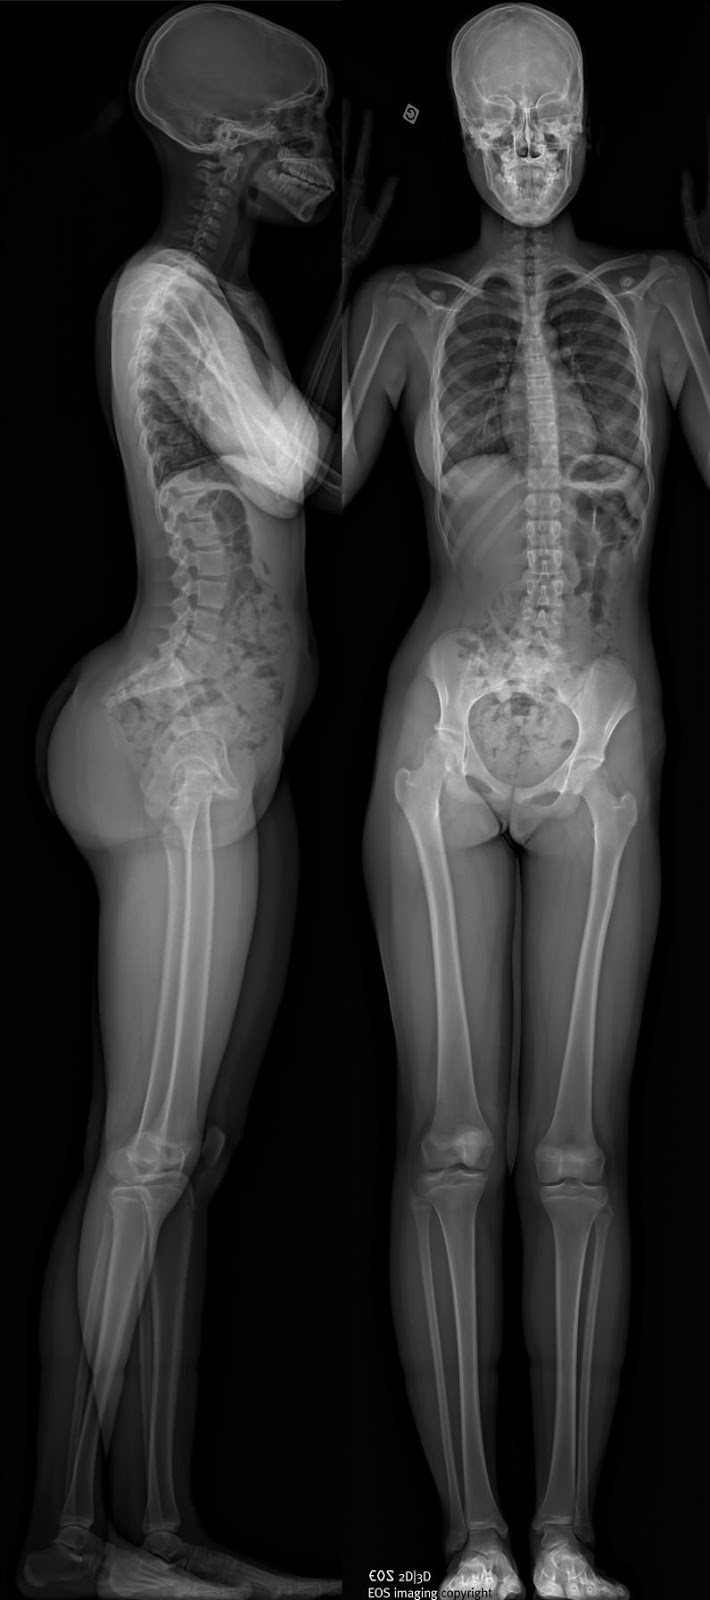

Специализированные клиники, в которых проходят лечение пациенты с деформациями позвоночника, используют метод рентгенографии. Тело человека снимают в положении стоя на длинную пленку без разрывов (панорамный снимок).

Так как в клинической практике оценки деформаций позвоночника наиболее удобен метод рентгенографии, ученые выяснили взаимоотношения между изменением центра тяжести и графическое отображение тела человека. Как раз для этого и нужны снимки всего позвоночника в положении стоя. Было установлено, что гравитационная линия всегда параллельна отвесу из седьмого шейного позвонка.

Так как наиболее выгодная позиция для оси позвоночника — положение рядом с гравитационной линией, то у сбалансированного позвоночника отвес из седьмого шейного позвонка на рентгенограмме в положении стоя проходит рядом с крестцом (в передне-задней и боковой проекциях) и через головки бедренных костей. Допустимым отклонением от крестца считается 4 см.

Чем дальше отклоняется крестец от головок бедренных костей в сторону, тем больше энергии приходится затрачивать мышцам на поддержание баланса. Увеличивается рычаг. Величину такого отклонения называют pelvic tilt (PT), т.е. наклоном таза к вертикали. Оценивают его по углу между линией, проведенной через центр замыкательной пластинки S1 позвонка и центр головок бедренных костей, и вертикальной линией (т.е. гравитационной линией тела человека). На картинке ниже этот угол обозначен оранжевым цветом.

С учетом того, что существуют разные анатомические варианты строения таза, положение крестца и головок бедренных костей различаются у разных людей. На рентгенограммах взаимоотношение между этими двумя элементами показывает pelvic incidence (PI). Это угол между между линией, проведенной через центр замыкательной пластинки S1 позвонка и центр головок бедренных костей, и перпендикуляром из центра замыкательной пластинки S1 позвонка.